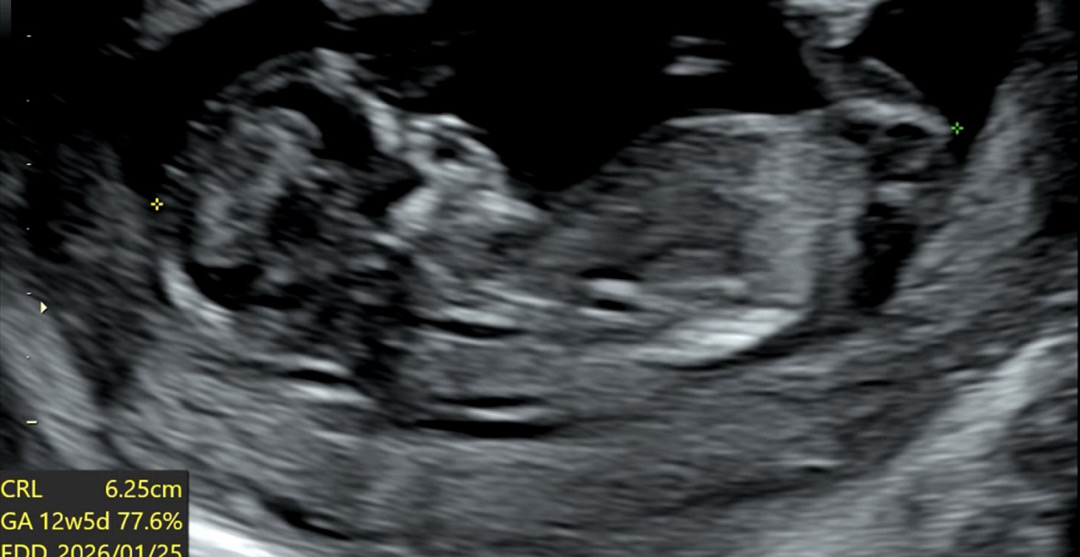

각도법 고수님들 유추 부탁드려요 💖🤗💖ㅜㅜ

아들일까요 딸일까요 ㅜㅜ 고수님들 알려주세요 ㅠㅠ